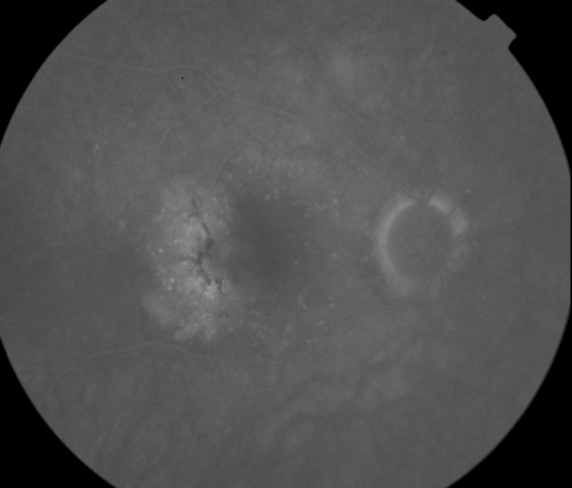

FUNDUS DESCRIPTION: |

OD OS |

OD Red-Free: Pre-Injection: Arterial: A-V: Venous: Recirculation: Late:

OS Red-Free: Venous: Recirc: Late:

Impression